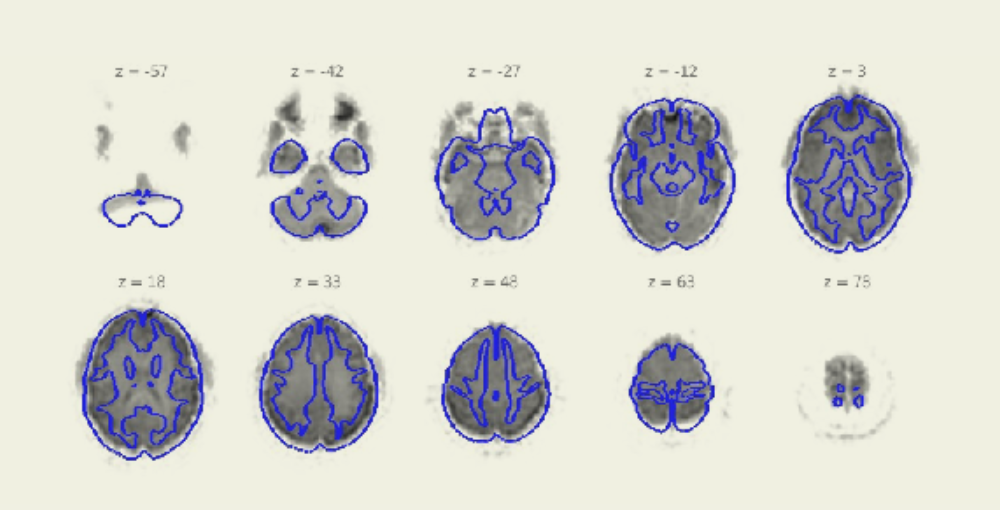

Looking through my "QA normalization: functional data + outline of MNI TPM template" output, quite a few of my subjects appear to have issues with the top and bottom most slices, with the bottom slices missing activation within the outline or having dark spots outside the outline (which I'm assuming are from the eyeballs) and the top slices having a sort of "halo" around the data (which I'm assuming is an artifact from the skull). I'm attaching one subject as an example. If I am using the the default explicit voxel-level analysis mask in my setup > options, is this data outside the brain going to removed for analysis and not a major concern, or are there other steps I need to take to fix my data?